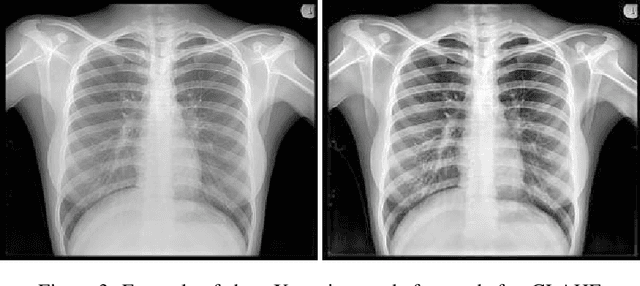

Abstract:Chest X-ray is the most common test among medical imaging modalities. It is applied for detection and differentiation of, among others, lung cancer, tuberculosis, and pneumonia, the last with importance due to the COVID-19 disease. Integrating computer-aided detection methods into the radiologist diagnostic pipeline, greatly reduces the doctors' workload, increasing reliability and quantitative analysis. Here we present a novel deep learning approach for lung segmentation, a basic, but arduous task in the diagnostic pipeline. Our method uses state-of-the-art fully convolutional neural networks in conjunction with an adversarial critic model. It generalized well to CXR images of unseen datasets with different patient profiles, achieving a final DSC of 97.5% on the JSRT dataset.